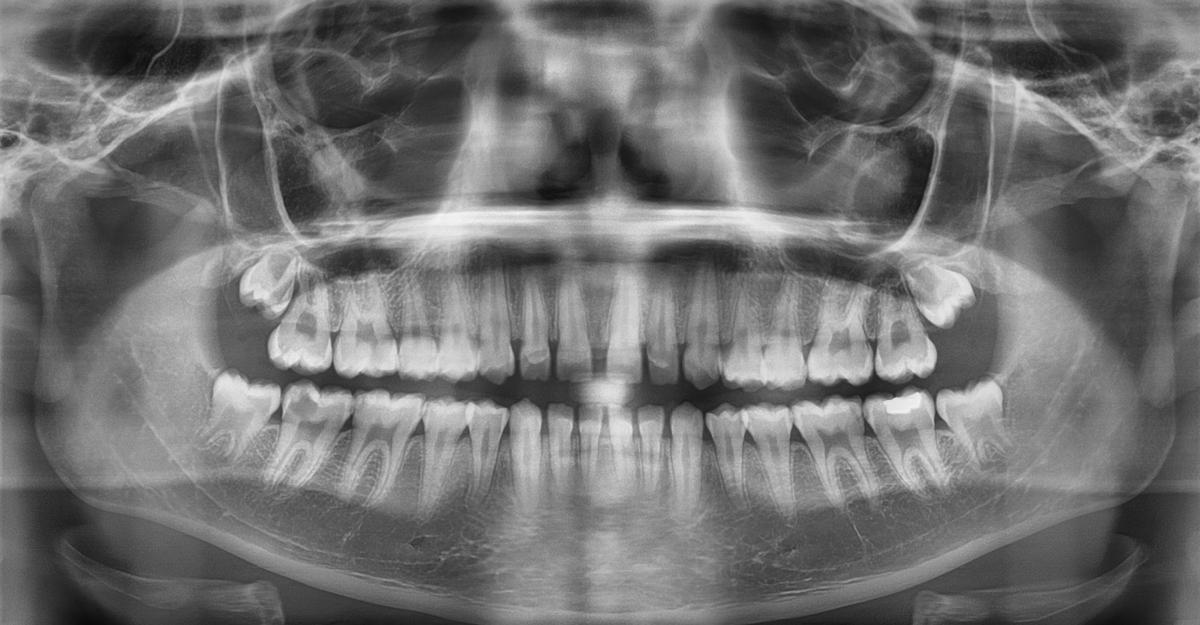

Radiografía dental utilizada en el trabajo. / UNIOVI

El modelo se entrenó con una muestra de 10.739 radiografías panorámicas dentales (ortopantomografías), de personas de 14 a 26 años, bien equilibrada entre hombres y mujeres, y procedentes de instituciones de doce países en cuatro continentes, "lo que garantiza la diversidad de la muestra y la robustez del sistema ante diferencias geográficas y biológicas". El método utiliza una red neuronal profunda denominada LAENet para estimar la edad de forma continua. Con este enfoque, el sistema obtuvo un error medio absoluto de solo 1,12 años, y una precisión del 88,38% al determinar si una persona supera o no el umbral de los 18 años.